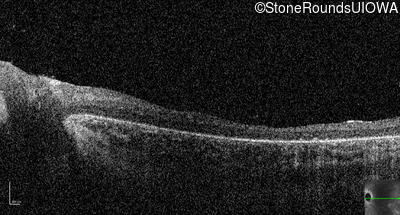

Optical Coherence Tomography - Left - 20/80

Exemplar / OCT Stack